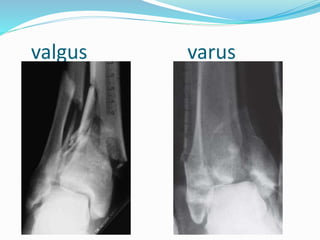

 It may be caused by shear loading (rotational or lower

energy impacts)

Leads to less degree of disruption of articular surface

valgus varus

MECHANISM  Pilon fracturesare most often caused by axial loading (high energy impacts)such as fall from height,motor vehicle accident -leads to high degree of disruption of articular surface and soft tissue affection  It may be caused by shear loading (rotational or lower energy impacts) Leads to less degree of disruption of articular surface